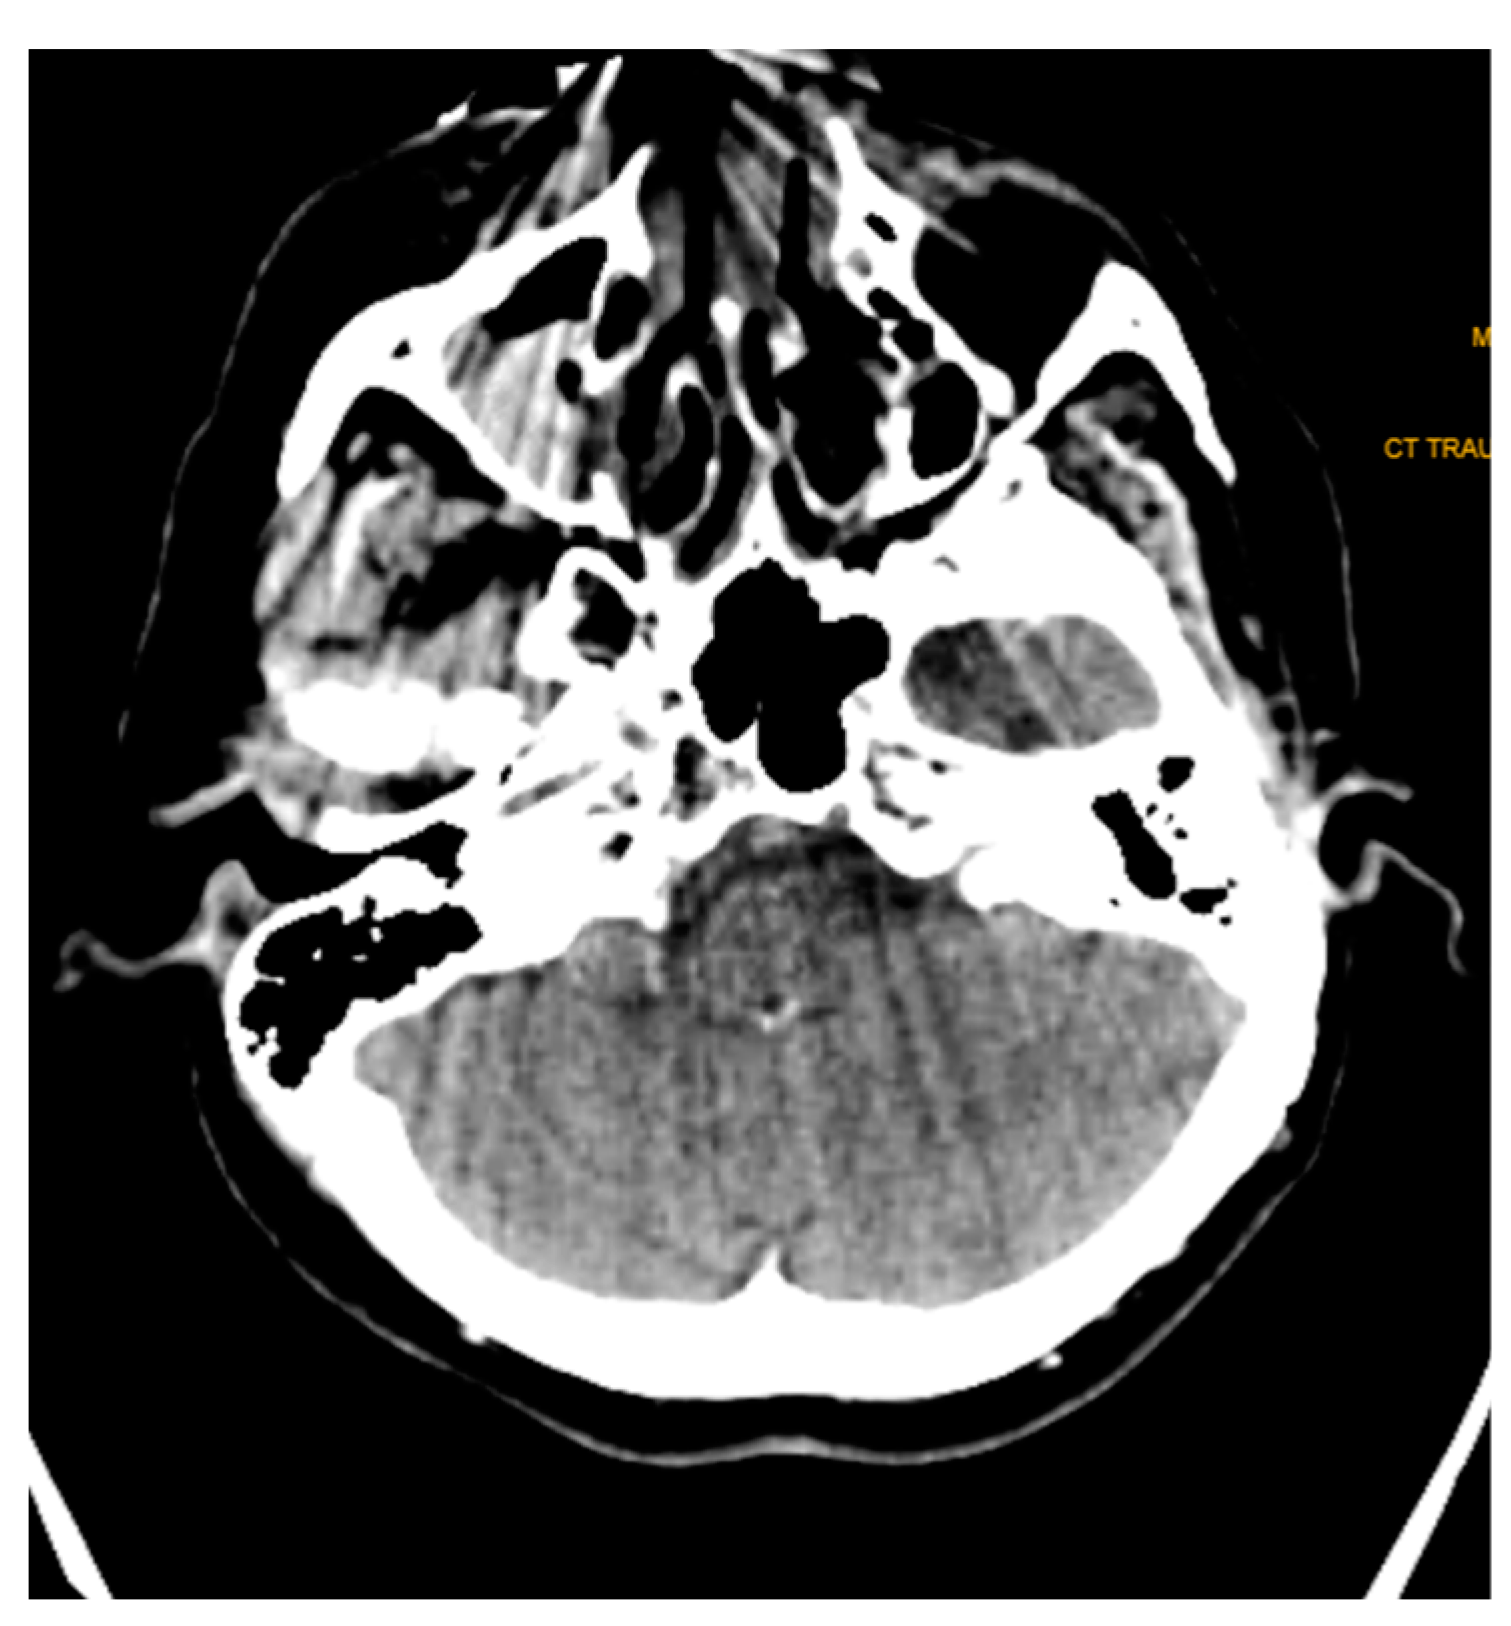

Streak and windmill artifacts greatly affect the scan images in CT. Windmill artifacts occur due to under-sampling along the Z axis, which usually occurs in the clavicle region and the base of the skull region, where drastic anatomical changes and differential Hounsfield units are present. A black streak artifact of the beam hardening effect greatly disrupting the diagnostic quality can be seen in Figure 7.

Figure 7. Black streak artifact of beam hardening effect evident in an axial section CT image. These are usually present at the base of the skull region, where drastic anatomical changes and differential Hounsfield units are present.